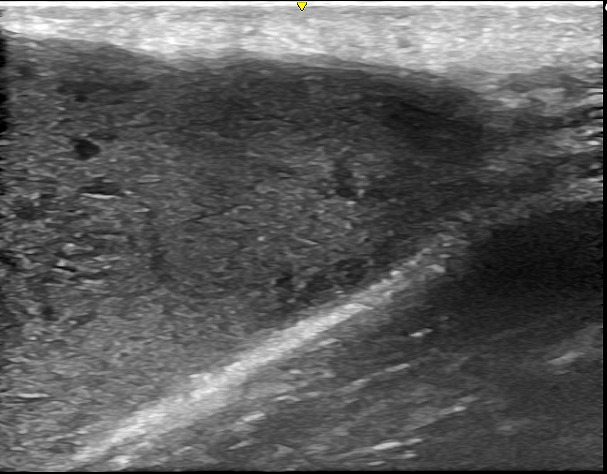

徐々に皮下腫瘍が大きくなったため、当院を受診されました。左肩に120mm大の巨大な皮下腫瘍があり、超音波検査の結果、典型的な粉瘤と診断されました。

術前